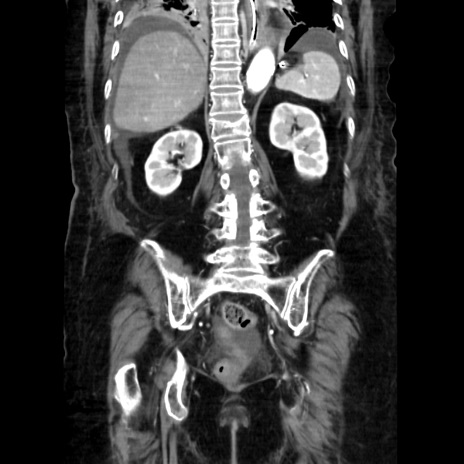

症例40(冠状断像)

【症例】90歳代女性

【主訴】腹痛・嘔吐

【現病歴】 食欲低下、嘔吐があり昨日他院受診。肺炎と診断され入院となる。入院後より腹部全体に圧痛あり。胃管留置され経過みていたが、症状持続するため、

当院転院となる。

【既往歴】胸椎圧迫骨折、胆石症

【身体所見】腹部:中央に激痛あり、圧痛あり、反跳痛不明

【データ】WBC 17100、CRP 18.82

冠状断像